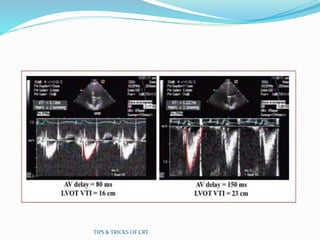

CRT OPTIMISATION -Aortic VTI

Method

 Objective:

 Identify the AV Delay that yields the maximum cardiac

output as determined by an aortic VTI measurement

 Procedure:

 Obtain continuous wave Doppler echo of aortic valve

outflow to obtain VTI measurement

 Record VTI values over a range of programmed AV Delays

 Program the AV Delay value that yields the maximum aortic

VTI

TIPS & TRICKS OF CRT

CRT OPTIMISATION -AorticVTI Method  Objective:  Identify the AV Delay that yields the maximum cardiac output as determined by an aortic VTI measurement  Procedure:  Obtain continuous wave Doppler echo of aortic valve outflow to obtain VTI measurement  Record VTI values over a range of programmed AV Delays  Program the AV Delay value that yields the maximum aortic VTI TIPS & TRICKS OF CRT